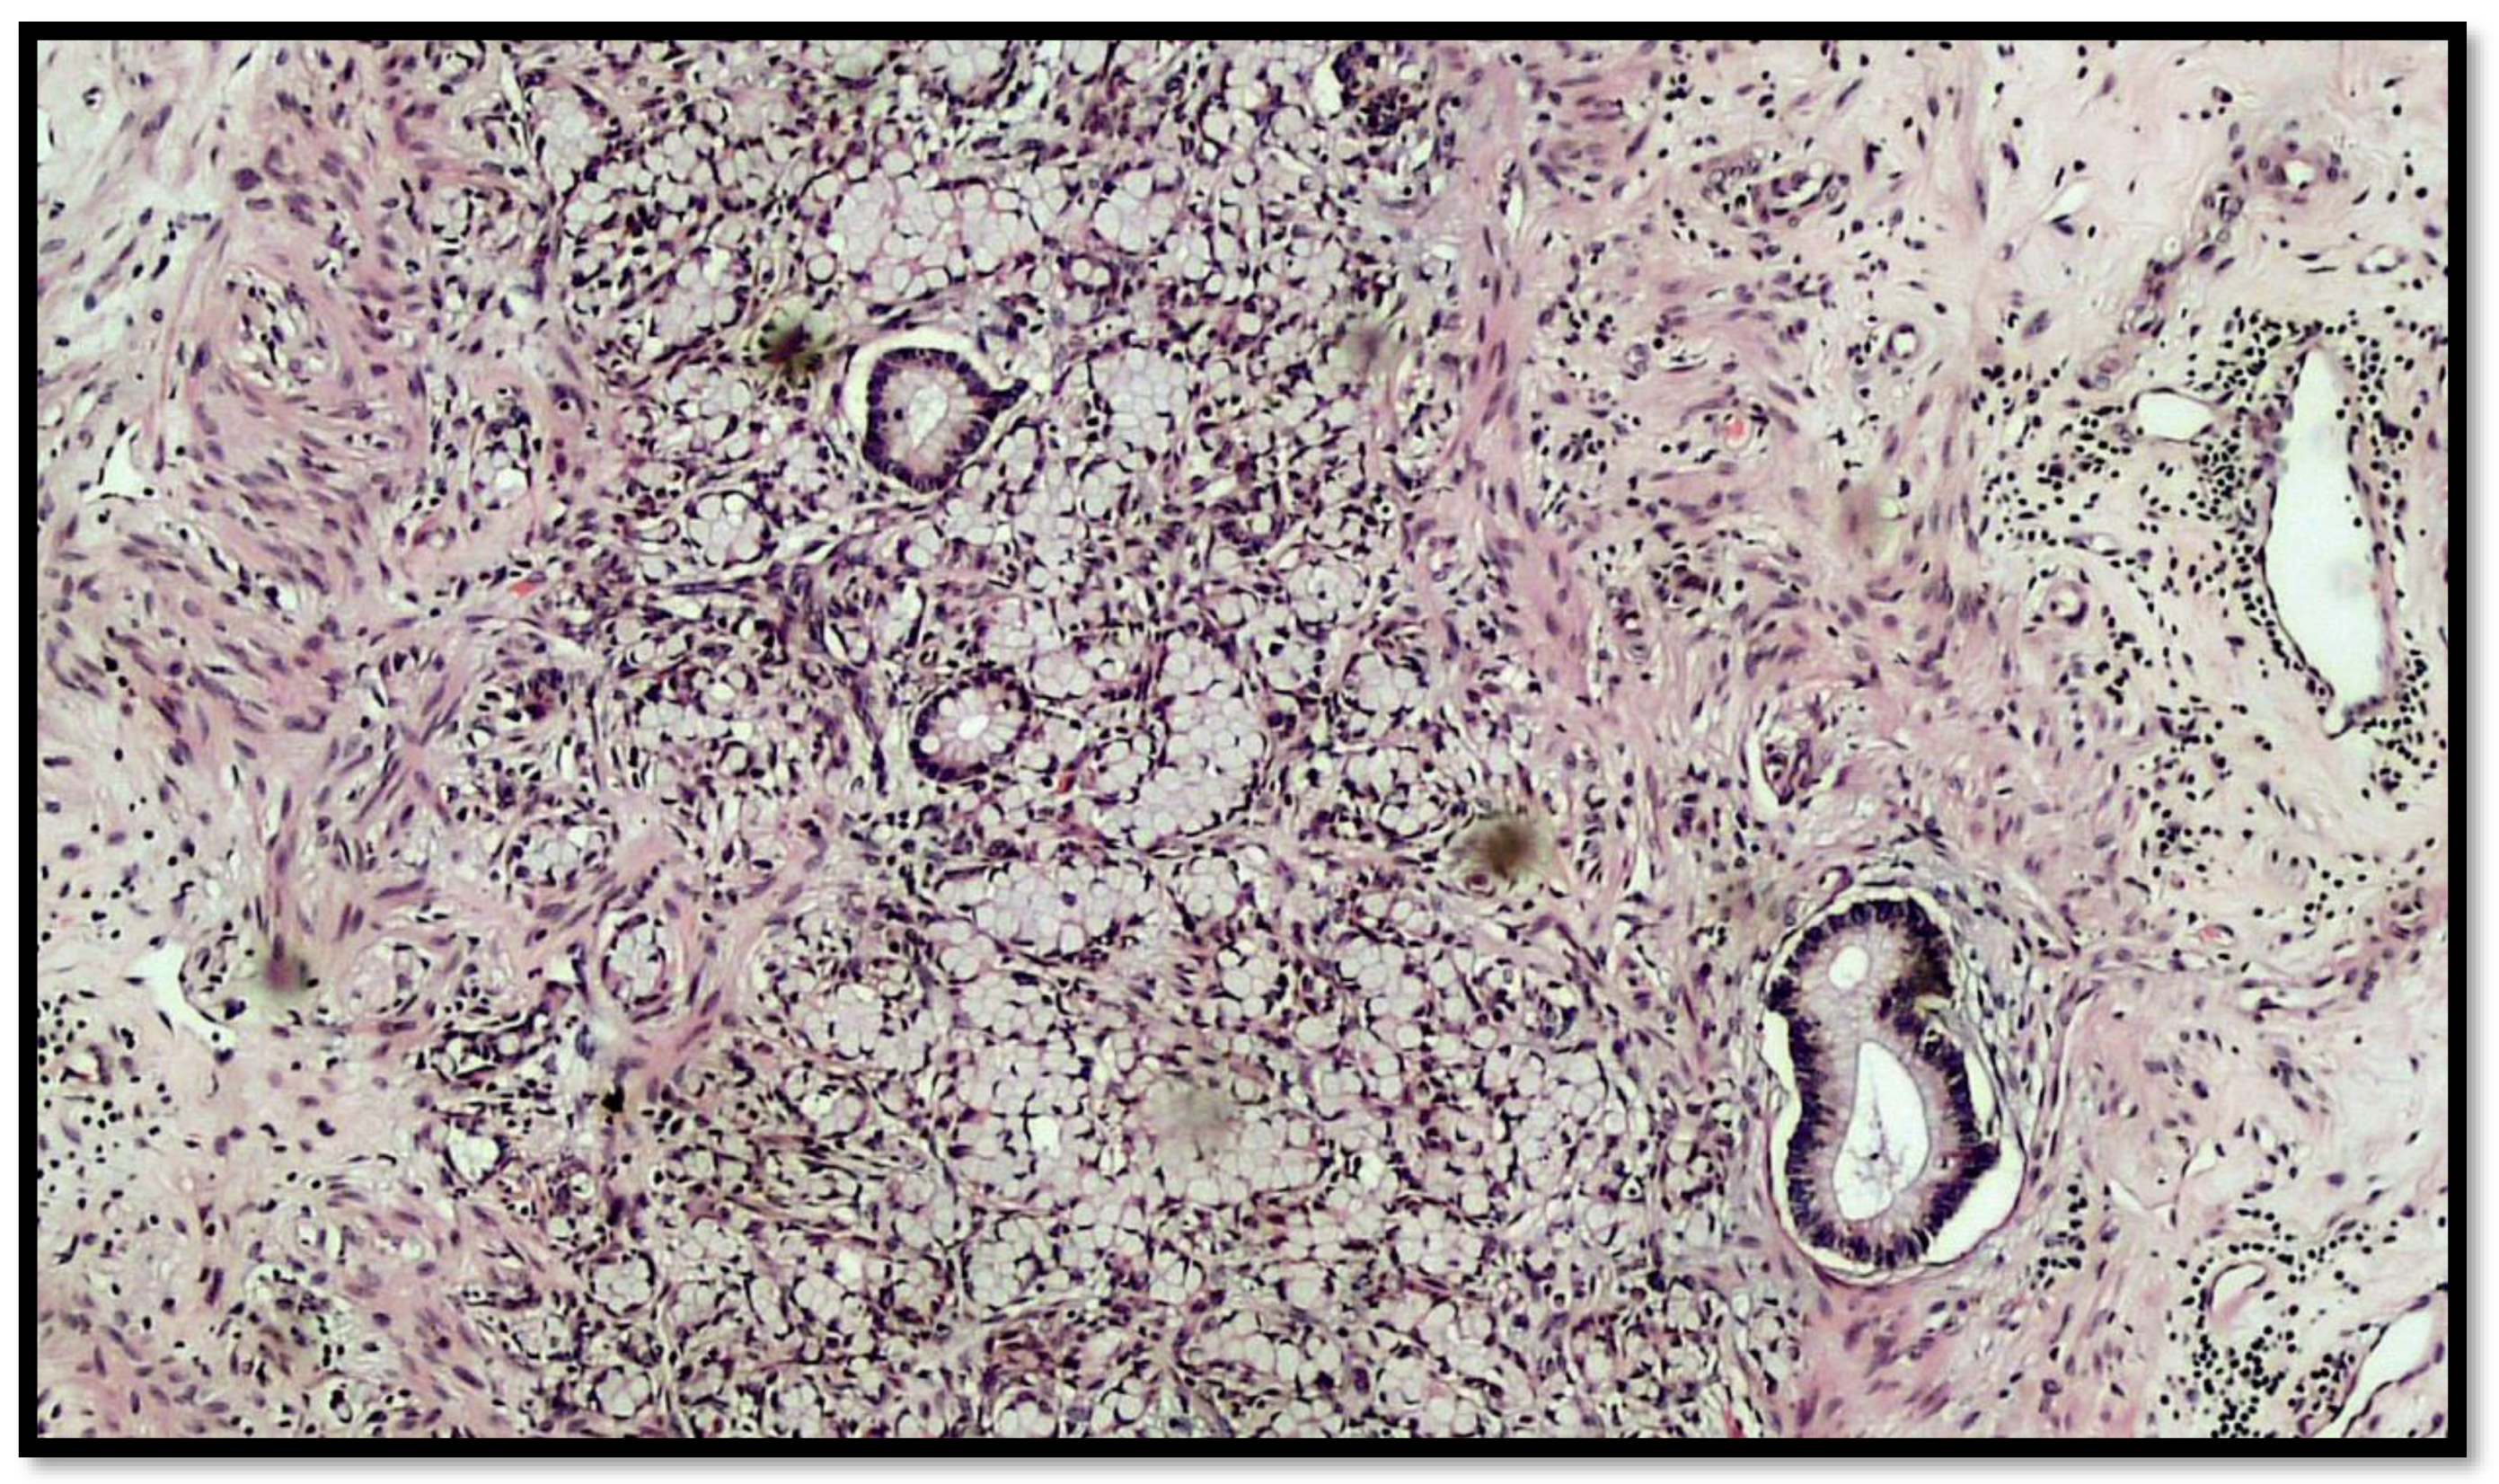

Figure 3.

Another photomicrograph showing goblet cell carcinoid and some glands in the muscular wall of the appendix. (Hematoxylin–eosin, original magnification 20×).